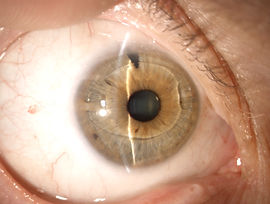

Cataratta bianca

IOL in camera anteriore

Il termine “cataratta” deriva dal greco (“catarréo”, discendere, cader giù) in quanto inizialmente si riteneva che l’opacamento della vista derivasse dalla “discesa di un velo” nell’occhio. In realtà oggi sappiamo che la cataratta è una opacizzazione, totale o parziale, del cristallino, lente naturale posta all’interno dell’occhio, dietro all’iride, che normalmente permette di mettere a fuoco sulla retina le immagini che osserviamo, a diverse distanze, attraverso un meccanismo muscolare dinamico noto con il nome di accomodazione.

Il decorso della cataratta nella maggior parte dei casi, non è prevedibile anche se normalmente ha una evoluzione lenta. Quando la cataratta riduce la qualità e la quantità visiva a tal punto da interferire con le normali attività quotidiane e lavorative, in rapporto alle esigenze del paziente, è richiesto l’intervento chirurgico. Procrastinare l’intervento aumenterebbe i rischi operatori legati ad una maggiore durezza del cristallino. In alcuni casi l’intervento dà luogo ad ulteriori vantaggi, contribuendo, per esempio, a ridurre la pressione intraoculare nei pazienti affetti da glaucoma.

INTERVENTO CHIRURGICO

L’asportazione del cristallino catarattoso comporta la perdita di un importante componente del sistema diottrico oculare. Mentre un tempo il difetto ipermetropico post operatorio veniva corretto con occhiali molto “spessi”, circa 12-13 diottrie, oggi è possibile inserire all’interno dell’occhio, un “cristallino artificiale” il cui potere viene calcolato, in base alle caratteristiche anatomiche e refrattive preoperatorie del singolo paziente, grazie all’esame biometrico che si avvale di strumenti e formule di calcolo sempre più sofisticati.

Generalmente l’intervento di cataratta viene eseguito in regime ambulatoriale e non è necessaria l’ospedalizzazione, dura circa 10-15 minuti, può essere eseguito in anestesia topica e/o locale, mediante la sola instillazione di un collirio anestetico oppure con delle iniezioni vicine all’occhio (anestesia peribulbare). Molto raramente è necessaria l’anestesia generale (es. pazienti non collaboranti). Attualmente esistono diversi metodi di rimozione della cataratta, la scelta della tecnica più appropriata per ogni singolo paziente è riservata al chirurgo. Nel corso degli anni, diverse metodiche chirurgiche sono state utilizzate, perfezionate ed evolute sintetizzandosi nella tecnica chirurgica attualmente più diffusa e praticata, la “facoemulsificazione”. Tale tecnica viene definita “mininvasiva” in quanto prevede delle “microincisioni” corneali (1,8-2,2 mm) che oltre alla ridotta invasività chirurgica consentono una maggiore sicurezza intra e post operatoria riducendo al minimo il traumatismo oculare, l’infiammazione e il rischio infettivo post chirurgico; nella maggior parte dei casi non è necessaria nessuna sutura, con conseguente riduzione dell’astigmatismo indotto chirurgicamente e una più rapida riabilitazione visiva. Lo strumento utilizzato, detto facoemulsificatore (da “pachos” lente), da cui il nome della tecnica, è composto da una sonda dotata di una punta sottile (da 1.8 a 2.5 mm di diametro) in grado di produrre ultrasuoni, che vibrando ad altissima frequenza consentono di frantumare il cristallino opaco in piccolissimi frammenti che a loro volta sono facilmente aspirati mediante un sistema automatico di irrigazione ed aspirazione continui. Dopo la rimozione della parte centrale, più dura, della cataratta, la corticale più periferica e “morbida”, viene rimossa con la sola aspirazione, mentre la maggior parte dell’involucro esterno del cristallino (la capsula) viene lasciata integra in quanto servirà ad accogliere il cristallino artificiale, mantenendo le condizioni anatomiche naturali dell’occhio. Il cristallino rimosso viene infatti sostituito da una “lente artificiale” - IOL- “Intra Ocular Lens” introdotta nell’occhio attraverso una speciale siringa (iniettore). La IOL non provoca reazioni di rigetto o allergia. È costituita da materiale di durata illimitata e non richiede cure o manutenzione. L’aspetto estetico è del tutto identico a quello naturale.

IOL (lenti intraoculari)

La chirurgia della cataratta, in questi ultimi anni, si è modificata profondamente trasformandosi in “chirurgia della cataratta refrattiva”, che va oltre la semplice eliminazione dell’opacità del cristallino; infatti, oggi il raggiungimento dell’emmetropia (assenza di difetti di vista) e l’indipendenza dagli occhiali è diventato uno degli obiettivi primari da raggiungere con questa chirurgia che ha portato allo sviluppo delle cosiddette "Premium IOLs", ossia lenti intraoculari customizzate in grado di andare oltre la semplice correzione del difetto sferico.

La correzione di eventuali difetti visivi, quali miopia ed ipermetropia, si ottiene a seguito di una serie di esami accurati, finalizzati a determinare il potere del cristallino artificiale che andrà ad eliminare gran parte del vizio refrattivo preesistente

La vista dopo l’intervento chirurgico dipende da una scelta consapevole della lente intraoculare che più si adatta alle proprie esigenze. Infatti attualmente in commercio esistono vari tipi di IOL che differiscono per diverse proprietà come la forma, le dimensioni, il materiale, l’angolazione delle anse, il contenuto di acqua, etc. di seguito alcuni esempi.

LENTI INTRAOCULARI STANDARD “MONOFOCALI”: sono progettate per ottenere un solo punto di messa a fuoco, solitamente si sceglie la distanza per lontano, lasciando all’occhiale la correzione del difetto per vicino. Consentono quindi, solo la correzione del difetto sferico. Tuttavia, in condizioni di basso contrasto o visione notturna la qualità della visione potrebbe non essere ottimale.

LENTI INTRAOCULARI TORICHE: Le IOL toriche, attualmente, rappresentano una delle soluzioni migliori per la correzione dell’astigmatismo, in quanto hanno un target refrattivo postoperatorio più prevedibile e possono correggere anche un astigmatismo di grado elevato; correttamente posizionata all’interno dell’occhio la lente compensa la distorsione della cornea, permettendo l’indipendenza degli occhiali nella visione per lontano nel postoperatorio. Le IOL toriche sono identiche a quelle monofocali, con l’unica differenza che hanno un orientamento preciso da rispettare; i pazienti candidati all’impianto di una IOL torica devono essere sottoposti ad una attenta valutazione diagnostica preoperatoria per una valutazione precisa del valore e dell’asse dell’astigmatismo corneale. È necessaria in fase pre o intraoperatoria la marcatura dell’asse stesso sul quale orientare la IOL; così durante l’intervento la IOL viene allineata con cura per evitare errori refrattivi.

LENTI INTRAOCULARI MULTIFOCALI: La IOL multifocale è progettata per ottenere un range di visione funzionale completo (vicino, intermedio, lontano) permettendo la messa a fuoco contemporanea di immagini poste a diversa distanza. Attualmente sono disponibili diverse tipologie di IOL multifocali, che differiscono fondamentalmente sul principio ottico che ne garantisce la multifocalità. Distinguiamo due tipi principali:

IOL multifocali refrattive: presentano zone, generalmente anulari, di potere refrattivo diverso che consentono di avere fuochi appropriati per vicino, per lontano e per la media distanza. L’energia luminosa dell’oggetto viene divisa in due o più fuochi principali in modo da ottenere immagini nitide alle distanze volute. Si ottengono più immagini di uno stesso oggetto ma una sola è a fuoco. Sono influenzate dal diametro pupillare, con disturbi soprattutto nelle attività o nella guida notturne.

IOL multifocali diffrattive: presentano una superficie anteriore liscia di tipo refrattivo utilizzata per correggere il difetto di focalizzazione per lontano ed una superficie posteriore diffrattiva, che presenta anelli concentrici che creano microscopici scalini (la cui altezza è compresa nell’ambito della lunghezza d’onda della luce), sfruttando il principio fisico della diffrazione per creare un secondo punto di messa a fuoco più anteriore, per la visione da vicino. Sono state recentemente perfezionate con le ottiche apodizzate: gli scalini diffrattivi sono modulati con una precisa riduzione dell'altezza dal centro alla periferia. Consentono una buona qualità visiva per lontano, e per vicino, meno alle distanze intermedie. Il vantaggio delle ottiche di tipo diffrattivo è che tutte le porzioni della lente contribuiscono alla creazione di entrambi i fuochi e quindi, a differenza delle lenti basate sull’ottica refrattiva, le variazioni del diametro pupillare non influiscono significativamente sul loro funzionamento. La presenza degli anelli diffrattivi può causare abbagliamento e aloni intorno alle fonti di luce.

Sono disponibili anche lenti miste Diffrattive/rifrattive e IOL multifocali TORICHE, per correggere contemporaneamente presbiopia e astigmatismo, oltre all’eventuale difetto sferico presente.

-

LENTI INTRAOCULARI ACCOMODATIVE: Attraverso un particolare forma della lente sembrano ripristinare il meccanismo naturale della messa a fuoco per vicino che si perde con l’età; sono lenti monofocali che cercano di riprodurre l’accomodazione naturale sfruttando il cambiamento della posizione della lente all’interno del sacco o un movimento dell’ottica grazie ad una particolare forma della lente stessa quando si contrae il muscolo ciliare. In questo modo riescono a mantenere una sola zona di fuoco per volta consentendo di eliminare alcuni fastidi, quali aloni e bagliori, tipici delle IOL multifocali ma la visione da vicino è meno precisa rispetto a queste ultime.